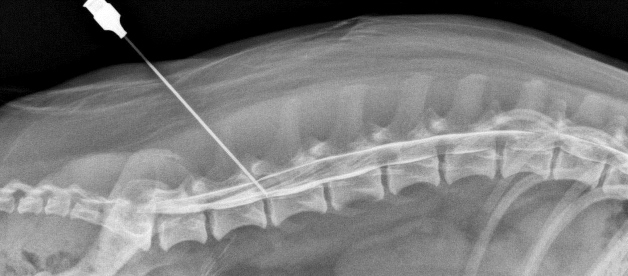

- блокады – надолго снимают боль, но не лечат;

В запущенных случаях (неконтролируемые мочеиспускание и дефекация, синдром конского хвоста) может потребоваться хирургическое вмешательство по декомпрессии и стабилизации пораженных сегментов позвоночника.

Для стабилизации поврежденного сегмента применяют спондилодез – слияние соседних позвонков при помощи специальной неподвижной конструкции (стержни). На место удаленного межпозвонкового диска ставится костный имплантат (костный материал берется или у донора, или формируется из кости самого пациента).

На заметку. Спондилодеза можно избежать. Хирурги добились многого в оперативном лечении остеохондроза. Вместо удаленного межпозвонкового диска можно установить искусственный и таким образом избежать полного обездвиживания сегмента. Операции на позвоночнике чреваты множеством осложнения, поэтому назначаются лишь в крайних случаях.